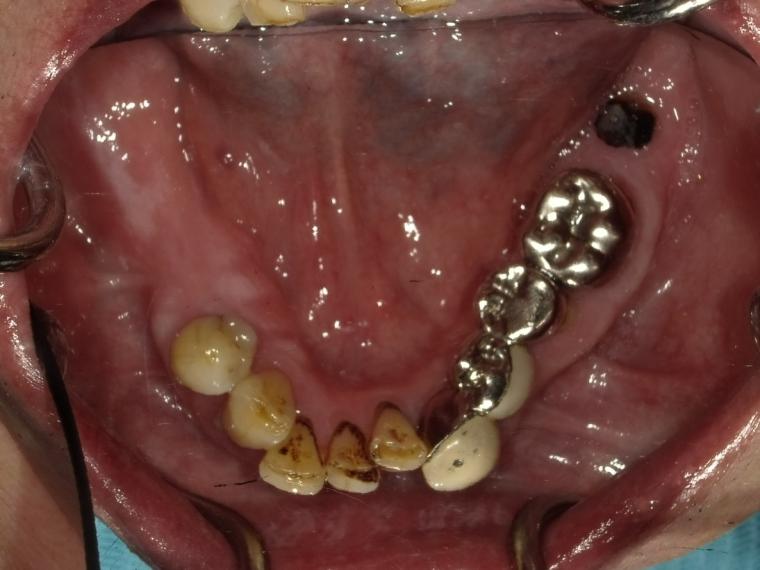

Before

62歳男性/オールオン4・6症例/インプラント埋込手術

インプラント希望でご来院された患者さんです。

美味く噛むことが出来ず美味しくお食事をしたいという主訴でご来院されました。

オールオン4・6というインプラント義歯での治療を選択されました。